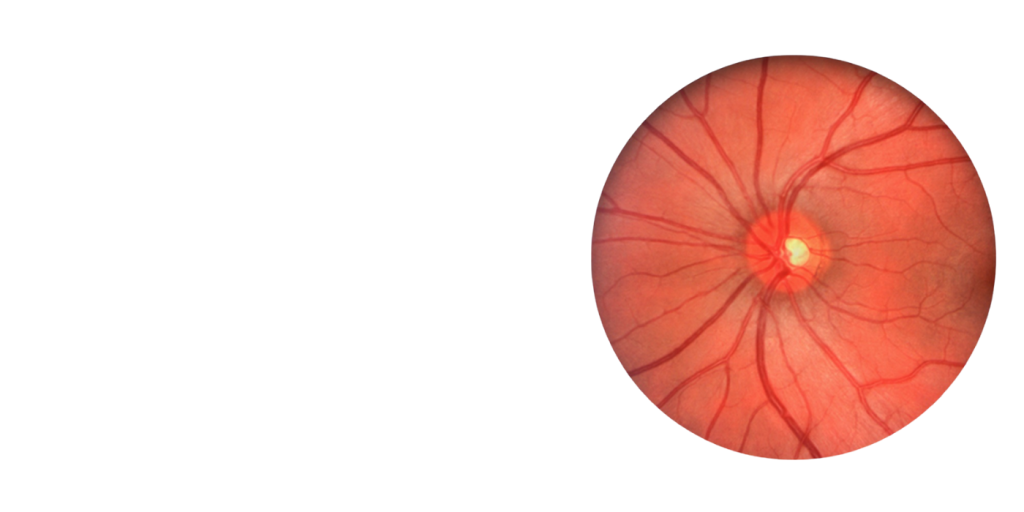

PACS and ophthalmic digital imaging systems, including imaging software alone, may only be offered for sale when clearance is completed and acknowledged in writing by FDA. And FDA mandates a vendor produce proof of 510(k) clearance upon request of relevant parties.

- Fundus Reading Centers require FDA clearance for imaging systems and PACS systems in order to be utilized in Clinical Studies

FDA clearance is the critical milestone in evaluating the safety and effectiveness of all medical devices in order to protect public health. In the case of diagnostic devices we use to treat patients in eye care, the 510(k) process is the defining standard demonstrating safety and effectiveness to FDA prior to offering these devices for sale.

FDA clearance for ophthalmic imaging and PACS systems requires meeting certain Consensus Standards such as ISO for optical performance, radiation (light) emissions safety, extensive software verification and validation, written DICOM and JPEG conformance, adherence to Good Manufacturing Practices and Quality Systems Regulations, strict quality production/